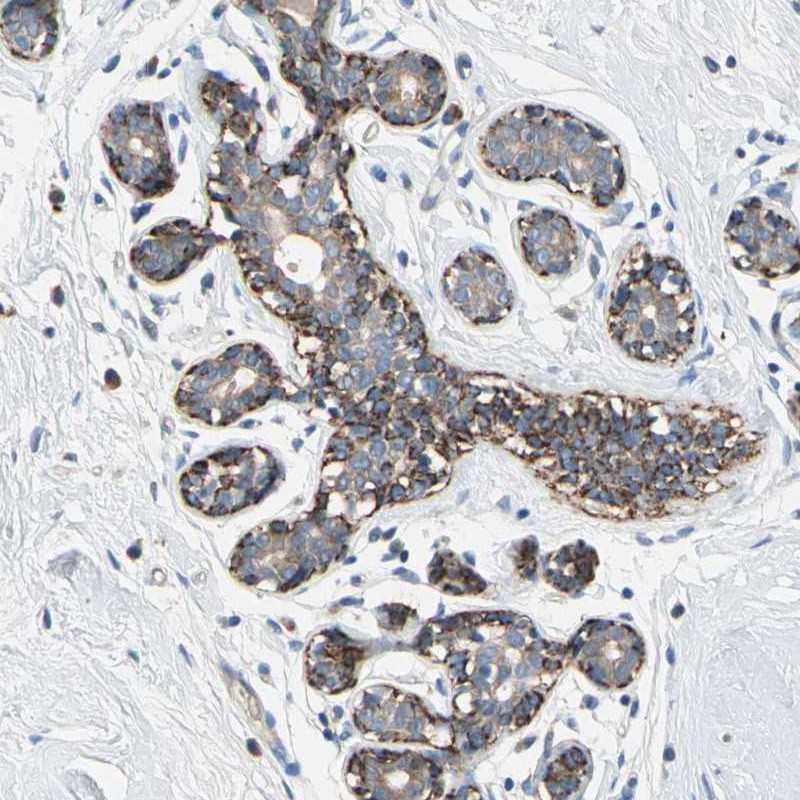

Immunohistochemical staining of human breast shows distinct cytoplasmic positivity in myoepithelium.